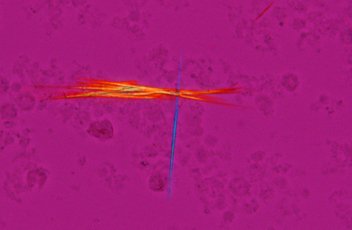

?敏感色偏光

通過改變干擾色可以識別尿酸結晶在有機體中的形成,非常適合痛風和假性痛風測試。

尿酸鈉結晶敏感色偏光附件